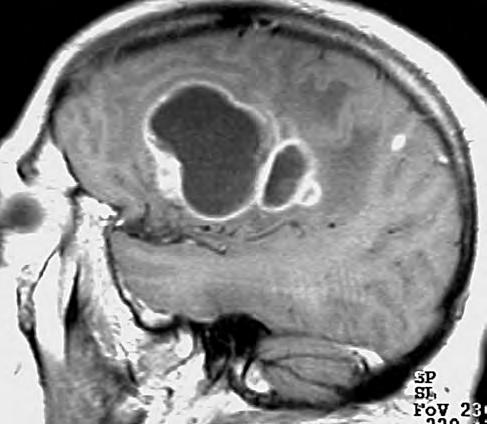

1.2 Glioblastom – ve srovnání s CT poskytuje MR vyšetření více detailů jak o struktuře nádoru, tak i o jeho prostorovém rozsahu, umístění a vztahu k mozkovým strukturám. Za příklad slouží parasagitální řez v T1 váženém čase po aplikaci kontrastní látky i.v.

CT nebo MR vyšetření je podstatné vědět, že vnativním zobrazení nemusí být tumor vždy zřetelný, proto je nutné provést vyšetření spoužitím kontrastních látek. Výsledek zobrazovacího vyšetření může svelmi vysokou pravděpodobností informovat opřítomnosti maligního expanzivního ložiska viz obr. 1.1., 1.2., 1.3. Takovýto nález je dostatečnou indikací koperačnímu zákroku. Vdětském věku je možné provést ultrasonografické vyšetření mozku.